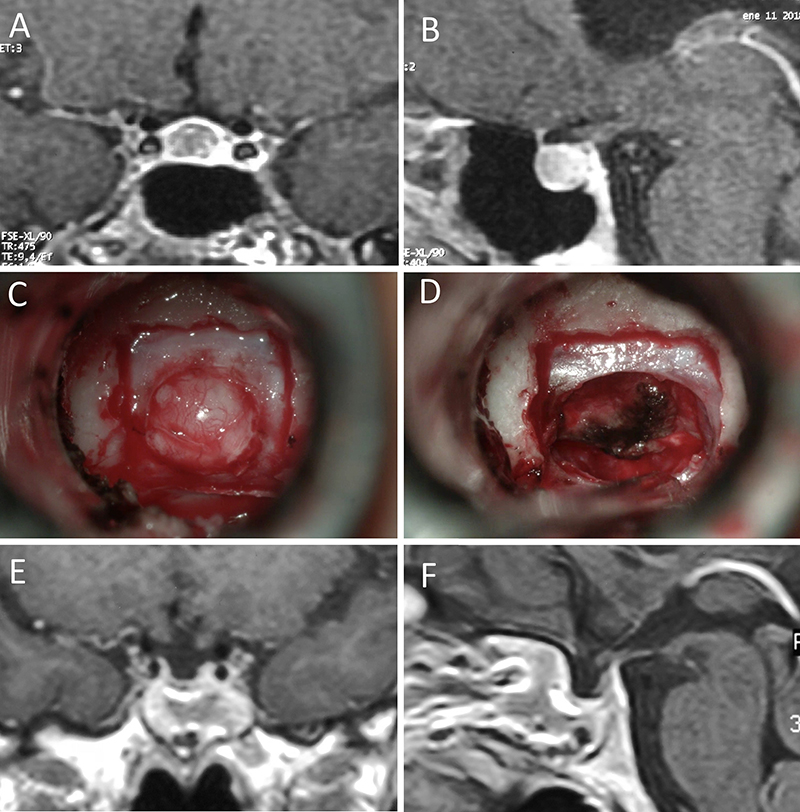

Figura 1: Macroadenoma no funcionante en mujer de 65 año

s. Se decidió la cirugía tras evidenciarse crecimiento en los controles. Evolucionó favorablemente desde el punto de vista clínico-radiológico. A-B: RM preoperatoria; C-D: intraoperatorio; E-F: RM postoperatoria.